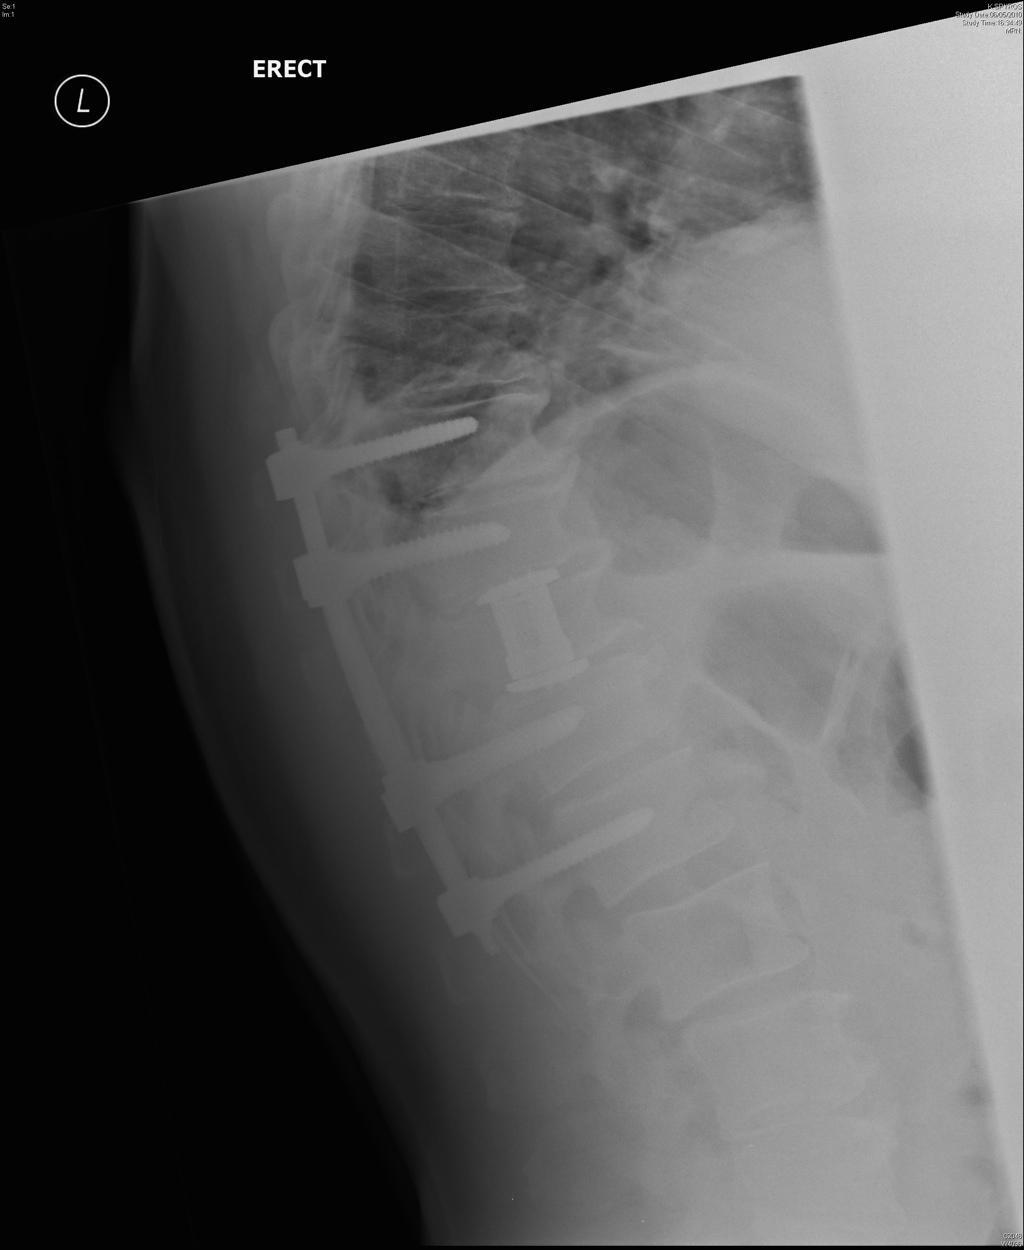

Spine Cancer Neck. But you can take steps to cope after your diagnosis. Most malignant vertebral tumors are caused by cancer that starts somewhere else in the body and spreads to the spine. A spinal cord tumor, also called an intradural tumor, is a spinal tumor that that begins within the spinal cord or the covering of the spinal cord (dura). Spinal metastasis (metastatic spinal cancer) happens when cancer in another part of your body spreads ( metastasizes) to. Learning that you have a spinal tumor can be overwhelming. Some of the cancers that may involve the spine. A tumor that affects the. S pinal tumors can involve the neck, back and lower back. They can begin in several different types of cells, including nerve. Cancer that spreads from an organ to another part. Find out all you can about your. A spinal tumor is an abnormal growth of cells within or surrounding your spinal cord and/or spinal column. Most spinal cancer occurs inside the spinal column and usually doesn’t affect the spinal cord.

Some of the cancers that may involve the spine. Cancer that spreads from an organ to another part. A spinal cord tumor, also called an intradural tumor, is a spinal tumor that that begins within the spinal cord or the covering of the spinal cord (dura). Find out all you can about your. Spinal metastasis (metastatic spinal cancer) happens when cancer in another part of your body spreads ( metastasizes) to. Learning that you have a spinal tumor can be overwhelming. A tumor that affects the. They can begin in several different types of cells, including nerve. S pinal tumors can involve the neck, back and lower back. Most malignant vertebral tumors are caused by cancer that starts somewhere else in the body and spreads to the spine.

Spine Cancer Neck But you can take steps to cope after your diagnosis. A tumor that affects the. But you can take steps to cope after your diagnosis. Cancer that spreads from an organ to another part. A spinal tumor is an abnormal growth of cells within or surrounding your spinal cord and/or spinal column. A spinal cord tumor, also called an intradural tumor, is a spinal tumor that that begins within the spinal cord or the covering of the spinal cord (dura). They can begin in several different types of cells, including nerve. S pinal tumors can involve the neck, back and lower back. Some of the cancers that may involve the spine. Most malignant vertebral tumors are caused by cancer that starts somewhere else in the body and spreads to the spine. Learning that you have a spinal tumor can be overwhelming. Spinal metastasis (metastatic spinal cancer) happens when cancer in another part of your body spreads ( metastasizes) to. Most spinal cancer occurs inside the spinal column and usually doesn’t affect the spinal cord. Find out all you can about your.